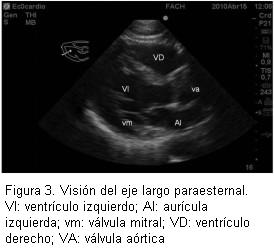

Los resultados de este taller demuestran claramente que se cumplió con el objetivo planteado al inicio: enseñar los principios básicos de ecografía transtorácica y ecografía para punción vascular. Esto se evidenció en la clara mejoría de los resultados de la prueba aplicada antes y después del taller (figura 3). Así con la realización de una introducción teórica y estaciones prácticas (figuras 4 y 5) se logra un significativo avance en la comprensión de la ecografía por parte de los anestesiólogos.

Se ha planteado que el examen ecocardiográfico transtorácico que realiza un anestesiólogo es completamente diferente al examen que realiza el cardiólogo y, por supuesto, no pretende de manera alguna reemplazarlo. Esto se explica porque el anestesiólogo busca resolver preguntas concretas con respecto a lo que ocurre con el corazón en el paciente en su perioperatorio: el estado de la volemia, la contractilidad y tamaño de las cavidades cardíacas. Existen varias publicaciones que avalan la utilidad de la ecocardiografía para los anestesiólogos. Uno de los primeros estudios fue hecho por el grupo de Sloth (6), que evaluaron a pacientes hemodinámicamente inestables en su postoperatorio y obtuvo imágenes satisfactorias por encima del 80% de los casos e imágenes que fueron útiles como guía y manejo de estos pacientes. Durante el preoperatorio se ha planteado la gran utilidad que puede tener la ecocardiografía para evaluar pacientes con presencia de soplos en el examen físico, con capacidad funcional no evaluable y aquellos pacientes con severa alteración de sus capacidades mentales (enfermedad de Alzheimer, deterioro senil) (7). En el intraoperatorio realmente puede ser útil para la monitorización del estado hemodinámico de manera no invasiva (8,9), que permite realizar nuevos diagnósticos, iniciar nuevas terapias y reemplazar otras formas de monitorización, como línea arterial o catéter venoso central. Otra indicación que puede resultar muy interesante es la alta utilidad que puede tener la ecografía durante las maniobras de resucitación cardiopulmonar, ya que en períodos muy breves de detención de las maniobras de masaje cardíaco externo, es posible visualizar a través de la ventana subcostal qué sucede realmente con el miocardio, y es así que se ha demostrado que no siempre el diagnóstico de actividad eléctrica sin pulso corresponde a esta entidad (10).

Las principales críticas al taller fueron la falta de claridad al explicar el tipo de transductor que debe utilizarse para cada procedimiento. Así, para realizar ecocardiografía transtorácica, se requiere de un transductor que alcance planos más profundos y por esto se utiliza uno cardiológico con frecuencias de 5 MHz. Para realizar punciones vasculares se requiere de un transductor lineal que tenga gran precisión y no es necesario que alcance grandes profundidades, por esto se utiliza un transductor lineal entre 12 y 15 MHz. Este último es el mismo que se utilizaría para una punción de nervio bajo ecocardiografía.

Además, todos los transductores tienen una marca que se correlaciona con la orientación de las imágenes en la pantalla. Se puede trabajar con diferentes angulaciones del transductor a 0°, 90° y todos los valores intermedios. También se puede realizar movimiento de “tilting” o balanceo que permite efectuar un barrido de las estructuras.